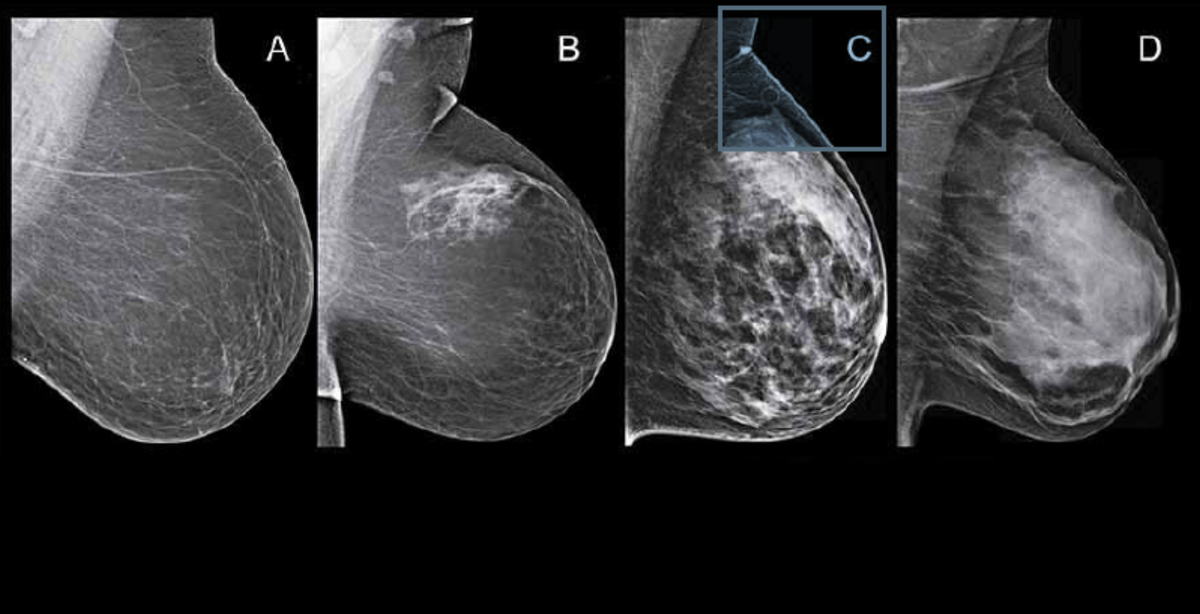

Маммография увидела фиброзно-кистозную мастопатию, а УЗИ - фиброаденому ...

МРТ молочной железы, магнитно-резонансная диагностика рака молочных желёз